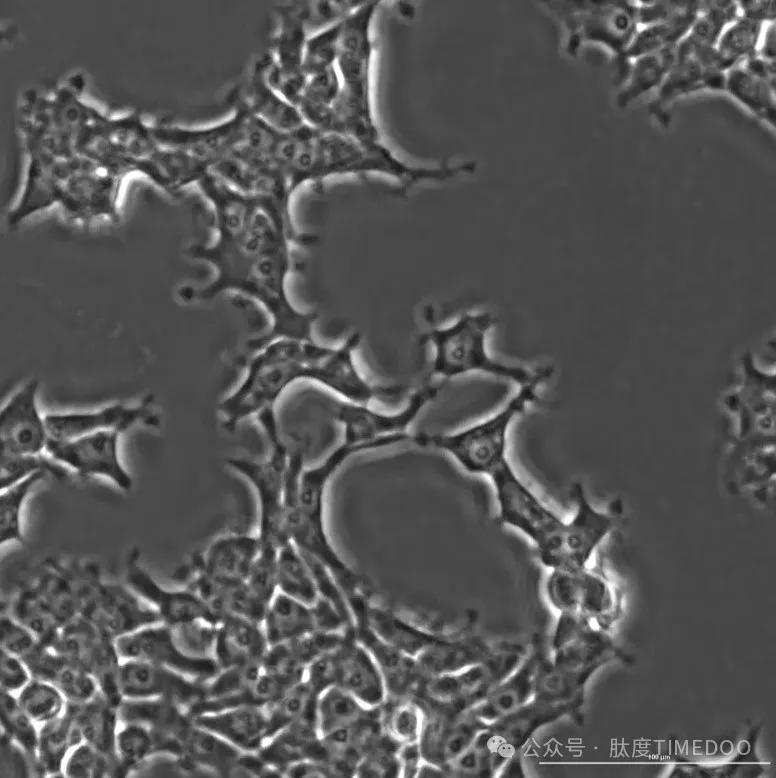

△OpenCRISPR-1編輯的人類細胞

在最新發(fā)布的研究中,他們描述了這一基因編輯器的生成和特性。他們發(fā)現(xiàn),當OpenCRISPR-1被引入HEK293T細胞時,它顯示出與目前流行的SpCas9相似的編輯效率,但具有更高的特異性,這意味著它可以更準確地編輯目標基因。更令人興奮的是,當OpenCRISPR-1與人工智能生成的去氨酶結合時,它能夠?qū)崿F(xiàn)堿基編輯,顯示出在一系列目標位點的強大編輯能力。